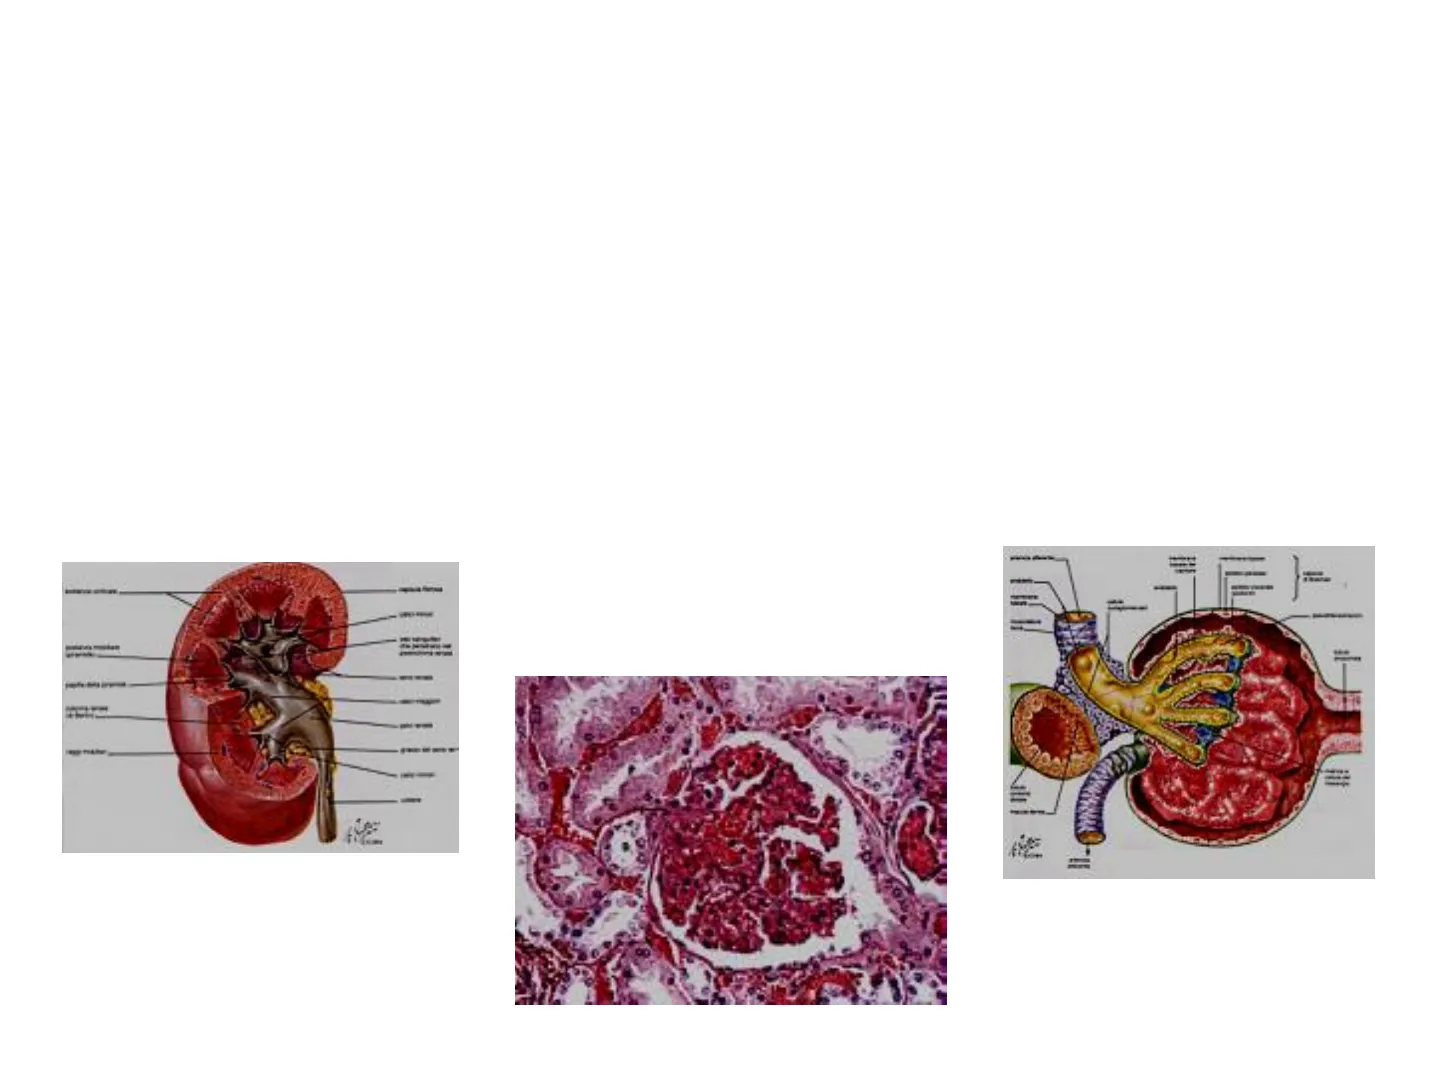

CORTICALE: disposta attorno alla midollare 2 ZONE MIDOLLARE:composta dalle PIRAMIDI RENALI, ognuna delle quali termina con una PAPILLA RENALE che sporge nel CALICE RENALE, il quale è un recesso della PELVI RENALE; quest'ultima convoglia nell'uretere l'urina prodotta. Cortex Glomerulus Medulla Loop of Henle Renal papilla Pyramid with nephrons and a collecting duct, which empties the urine into the renal pelvis Renal artery and renal vein Renal pelvis Ureter scanvetpress.com UNITA' FUNZIONALE 5 Renal papilla Renal capsule Renal medulla Renal cortex NEFRONE IL NUMERO DI PIRAMIDI DIPENDE DALLA SPECIE

1) CORPUSCOLO RENALE (capillari glomerulari/glomerulo e capsula di Bowman) 2) TUBULO CONTORTO PROSSIMALE (TCP) 3) ANSA di HENLE (tratto discendente e tratto ascendente sottile e spesso) 4) TUBULO CONTORTO DISTALE (TCD) 5) DOTTO COLLETTORE

Nefrone iuxtamidollare: nefrone ad ansa Nefrone corticale (il tipo di nefrone lunga importante nella creazione del gradiente osmotico verticale nella midollare renale Glomerulo più abbondante - circa l'80% di tutti i nefroni) Tubulo distale Capsula di Bowman Tubulo prossimale Tubulo distale Tubulo prossimale Corticale renale Midollare renale Ansa di Henle Ramo discendente dell'ansa di Henle Dotto collettore Ramo ascendente dell'ansa di Henle Altri nefroni che si svuotano nello stesso dotto collettore Vasa recta (Alla pelvi renale) (Per una migliore visualizzazione, le dimensioni dei nefroni sono state grossolanamente esagerate e i capillari peritubulari, a eccezione dei vasa recta, sono stati omessi.)

NEFRONI CORTICALI: glomerulo, TCP, TCD e quasi tutta l'ansa nella corticale. Solo l'apice dell'ansa penetra nella midollare (anse corte). NEFRONI IUXTA-MIDOLLARI: glomerulo, TCP, TCD nella corticale; l'ansa origina nella corticale, ma si spinge in profondità nella midollare, fino quasi alla punta della papilla renale (anse lunghe).